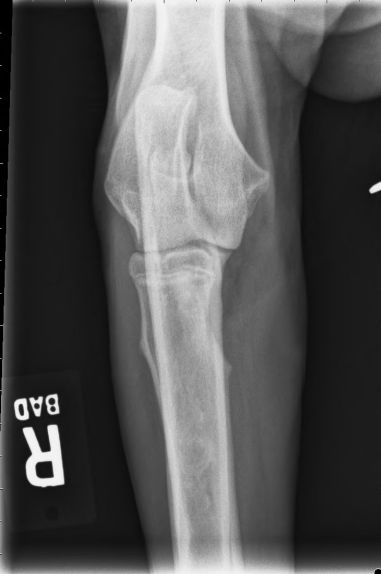

사진 모음

- arrow : 두꺼워진 골막

- arrowhead : 뿌옇게 보이는 골수관

- 범골염 증상 (비교적 명확)

- 범골염 증상